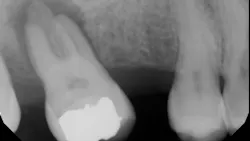

The goal of getting the tooth treated with a root canal or root canal retreatment is reduction of the bacteria and removal of the food source that helps bacteria thrive (pulp tissue and inflammatory proteins). The bone will fill back into the hole or osseous defect once the tooth canals are treated and the infection is removed (figure 3). Depending upon the size of the bone lesion, healing may take anywhere from three to 12 months.